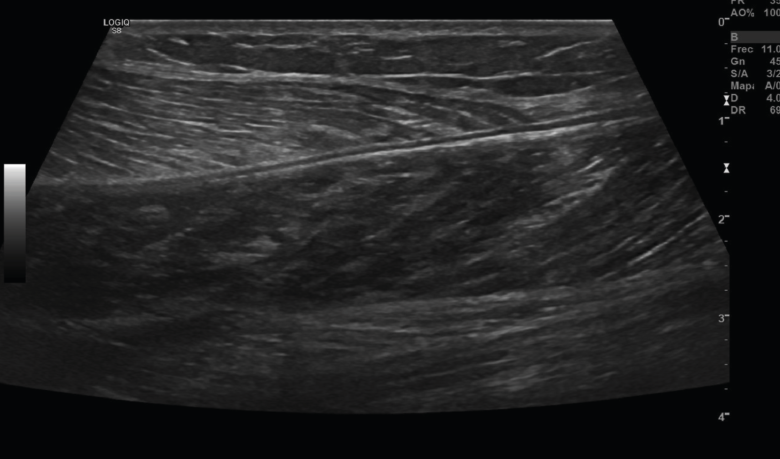

Figura 11. Corte sagital de una ecografía de pierna: imagen de fibras musculares normales del gemelo.

El músculo sano, ecográficamente, presenta una ecogenicidad inferior a la del tejido celular subcutáneo y una disposición de finas líneas paralelas ecogénicas, múltiples, en cortes longitudinales, en “pluma de ave”.

Se describen 4 grados de lesión muscular: grado 0, con ecografía negativa a pesar de tener clínica sugestiva; grado 1, con hiperecogenicidad en la lesión; y los grados 2 y 3, con regiones hipoecoicas por líquido adyacente a las fibras musculares. Cuando hay cicatrización, desaparece la región hipoecoica(8)(Figuras 11, 12, 13 y 14).